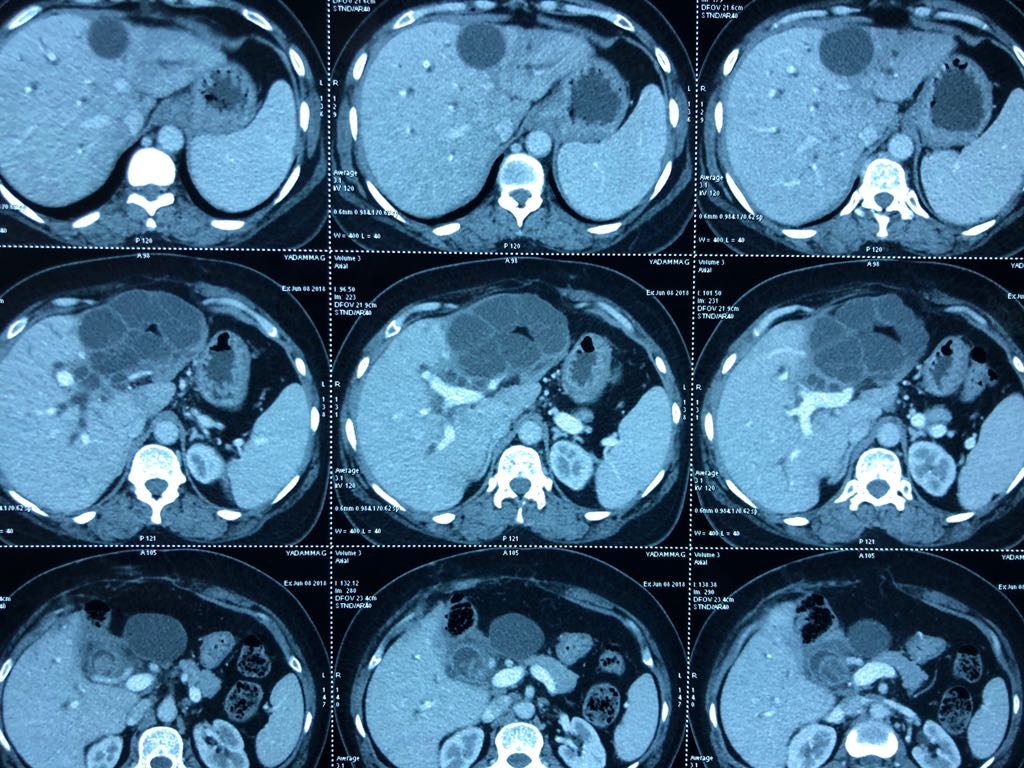

65 years of man type 3A hilar cholangiocarcinoma (complex hepatobiliary malignancy) with deep jaundice

SIX STEPS TO SUCCESS IN A ROLLER COASTER COVID CHALLENGE

- STEP 1: Left PTBD (to bring down jaundice)

- STEP 2: portal vein embolisation to allow growth of the small remnant left liver

- STEP 3: Right sided anterior and posterior PTBD to control persistent fever after initial intervention.

- STEP 4: admitted for surgery COVID positive CT CO-RADs 5 managed medically

- STEP 5: after 3 weeks waiting and repeat COVID PCR negative (couldn’t wait longer for risk of catheter dislodgement while waiting) underwent an Extended Rt hepatectomy with caudate lobectomy bile duct excision Left hepaticojejunostomy

- STEP 6: despite all the trials& tribulations and 7 hr surgery patient had a smooth recovery discharged by D6. An extremely satisfying result in a very difficult malignancy and a super motivated patient.